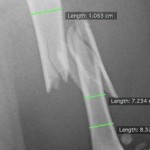

しかも粉砕骨折・・・

よくレントゲンをみてみると縦割れも起こしています。

やはり粉砕しているので単純骨折に比べると難易度は高くなります。

今回はプレートを用いて手術を実施しました。

ばらばらになっている骨片を一つ一つ集めて(ラグスクリュー、サークラージワイヤー)大腿骨全域にプレートで固定しました。